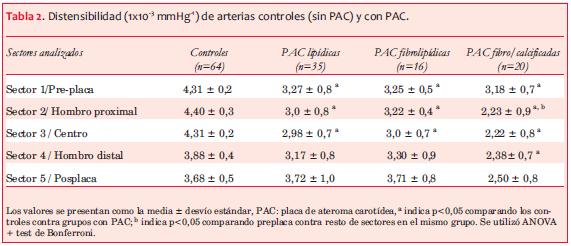

Se incluyeron 71 PAC (G1), de las cuales 35 se clasificaron como lipídicas, 16 como fibrolipídicas y 20 con contenido mayoritariamente fibroso/calcificado (tabla 2). Todas las PAC incluidas presentaban entre 15% y 45% de estenosis luminal, sin compromiso significativo del flujo arterial.

En la tabla 2 se presenta el valor medio y DE de la distensibilidad arterial para cada uno de los sectores estudiados en sujetos con PAC y arterias control, considerando cada una de ellas como una unidad de estudio independiente y separadas según su composición en los tres grupos mencionados. En la figura 7 se exponen dichos valores en forma gráfica para su mejor apreciación.

En forma general, los grupos de PAC estudiados mostraron diferencias en cuanto a la distensibilidad local a lo largo del eje longitudinal con respecto a las arterias controles (figura 7). La distensibilidad local de las arterias controles, por su parte, evidenció una tendencia global al descenso gradual (aumento de rigidez local) desde los sectores proximales a los distales. Todos los grupos de las arterias con PAC partieron de un punto de distensibilidad menor al grupo control en los sectores preplaca. No se evidenciaron diferencias estadísticamente significativas de distensibilidad entre los grupos con PAC en dicho sector. Las PAC con componente lipídico (FL y L) tendieron a presentar valores intermedios en el perfil de distensibilidad de los sectores 2-4 con respecto a las arterias control y grupo de placas FC.

El grupo de PAC FC evidenció el mayor grado de cambio de distensibilidad a nivel del hombro proximal. Empero, como se muestra en la figura 7, las placas con componente lipídico mostraron un comportamiento biomecánico homogéneo entre los sectores sucesivos estudiados, sin diferencias significativas y con una tendencia a aumentar su distensibilidad (“normalizarse”) en el sector posplaca. Las arterias con PAC FC mostraron aumento de la rigidez local a nivel del hombro distal y más allá de la placa en consideración.

Las diferencias biomecánicas carotídeas más notorias fueron evidenciadas fundamentalmente en el sector del hombro proximal con respecto al sector arterial adyacente (figura 7, tabla 2). En concreto, nuestros resultados evidencian un cambio significativo de la distensibilidad del sector preplaca con respecto al hombro proximal en las PAC FC, con valores de rigidez arterial en el hombro proximal superiores a los encontrados en el sector preplaca. Contrariamente, las PAC con componente lipídico no presentaron dicho cambio, encontrando valores comparables en dichos sectores y corriente abajo.